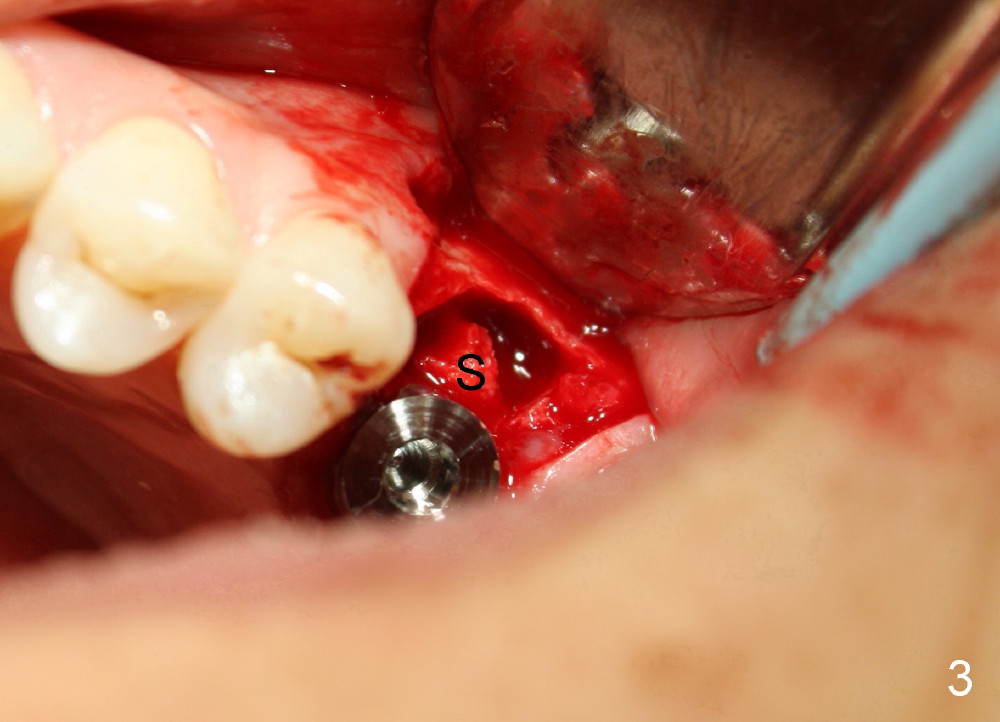

Is This Implant Nude in the Sinus (Fig.4)?

A 49-year-old lady has toothache at the upper left 1st molar (Fig.1).  Removal of the occlusal amalgam reveals crack lines (Fig.2).  After atraumatic extraction (sectioning), osteotomes are used to form osteotomy in the septum (Fig.3 S).  Finally the osteotomy seems to drop into the palatal socket.  No bone graft is used.  The socket is closed by elavating the buccal flap (Fig.3) and severing the periosteum.  Periodontal dressing is applied for wound protection (Fig.4 P). Is the implant in the sinus (S)?